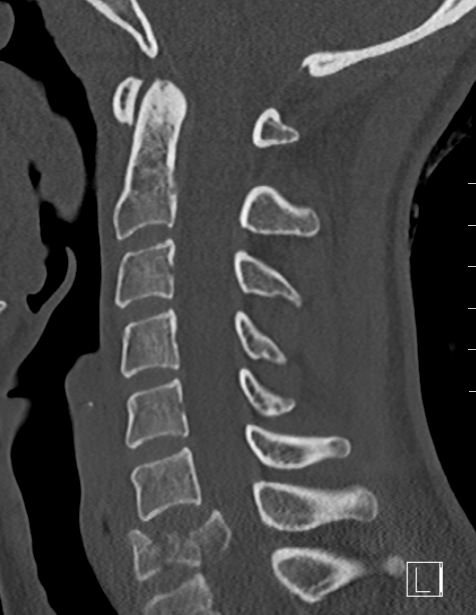

CT

X-ray

Lateral

- > 50% anterior column loss of height

- loss of posterior vertebral height